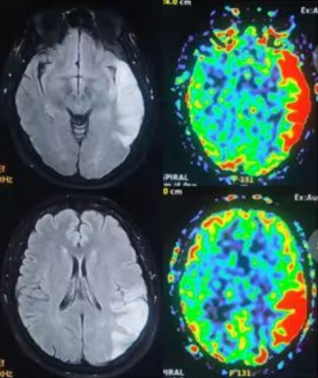

3.0T高端磁共振:这台先进的磁共振设备不仅具有超高的分辨率,还能进行不打药灌注(ASL),颅内血管壁高清成像,突破了传统影像学的局限。